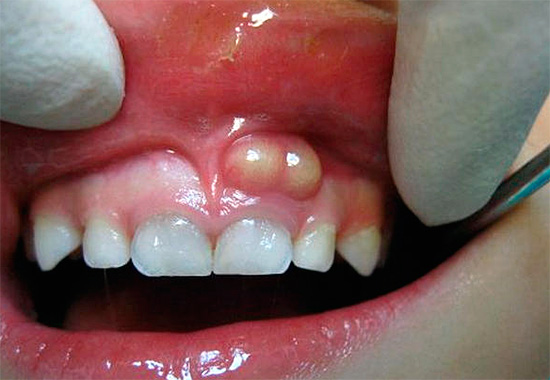

- La parodontite è un'infiammazione dei tessuti che circondano la radice del dente (l'apparato legamentoso che tiene il dente nell'incavo), che si manifesta più spesso con un processo purulento con ingrossamento e gonfiore delle gengive vicino al dente malato o comparsa di fistole sulle gengive, da cui il pus scorre nella cavità orale.